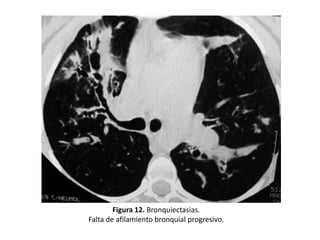

• En el caso de que el bronquio transcurra paralelo al

plano de sección, la dilatación anormal se reconoce por

la falta del progresivo afilamiento bronquial

– Ausencia de reducción del calibre bronquial desde la

división dicotómica. (Figura 12)

Figura 12. Bronquiectasias.

Falta de afilamiento bronquial progresivo.